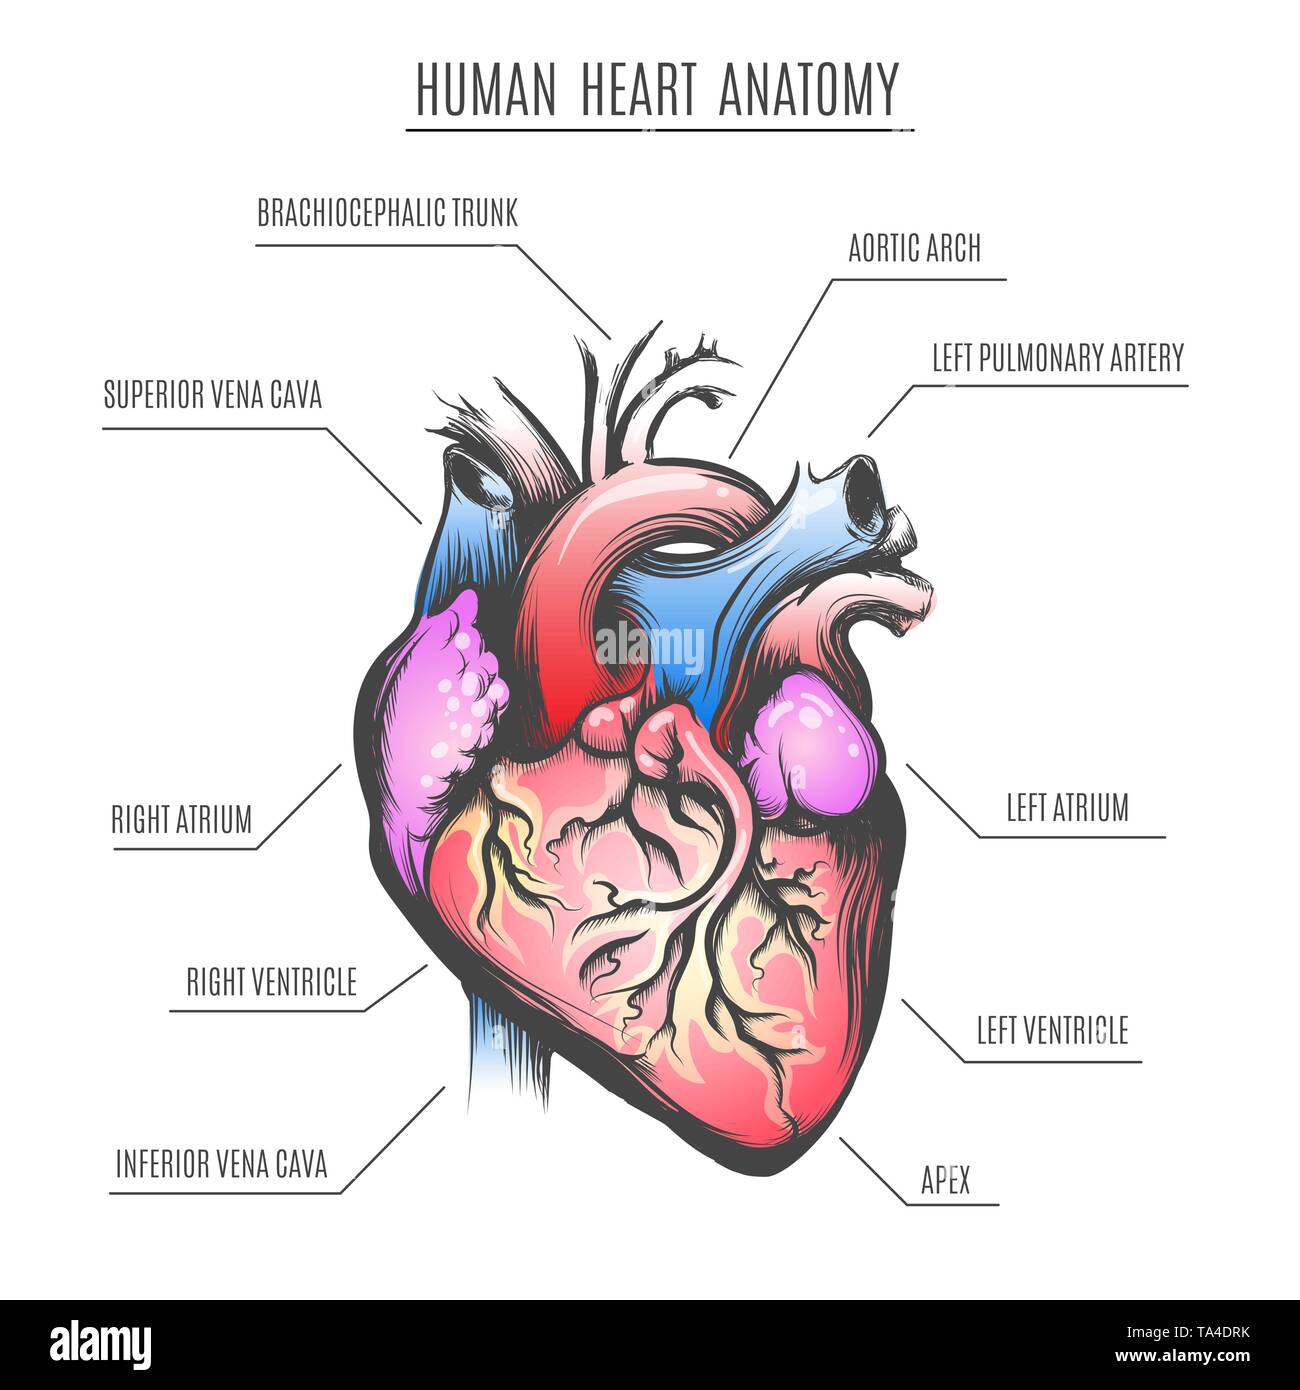

Human Heart Anatomy poster. Vector illustration. Stock Vectorhttps://www.alamy.com/image-license-details/?v=1https://www.alamy.com/human-heart-anatomy-poster-vector-illustration-image247190375.html

Human Heart Anatomy poster. Vector illustration. Stock Vectorhttps://www.alamy.com/image-license-details/?v=1https://www.alamy.com/human-heart-anatomy-poster-vector-illustration-image247190375.htmlRFTA4DRK–Human Heart Anatomy poster. Vector illustration.